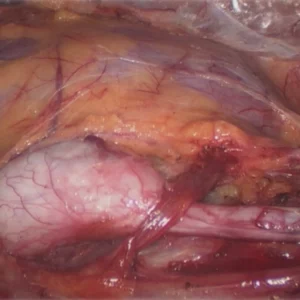

Crossed fused ectopic kidney

Crossed fused ectopic kidney is an unusual congenital malformation of the urinary tract. The condition is usually identified in the autopsy specimen rather than in a general clinical scenario. In this condition, both kidneys are located on one side of the midline and are fused with each other.